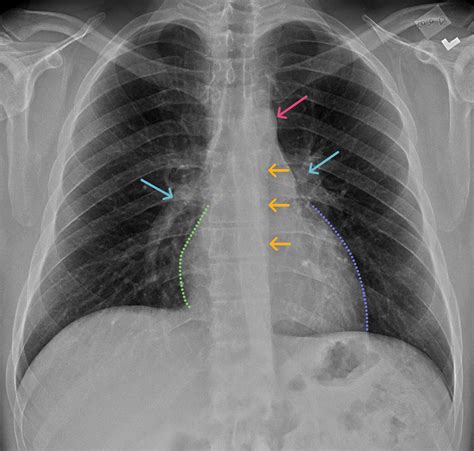

Interpreting a Normal Chest Ray

Interpreting a Normal Chest Ray involves examining the images for any abnormalities. Radiologists look for signs of:

• Lung Conditions: Pneumonia, lung cancer, or emphysema.

• Heart Issues: Enlarged heart, fluid around the heart, or heart failure.

• Bone Abnormalities: Fractures, tumors, or infections in the ribs or spine.

• Other Structures: Enlarged lymph nodes, pleural effusions, or foreign objects.

Common Findings in a Normal Chest Ray

A Normal Chest Ray typically reveals the following structures and conditions:

Structure/Condition Description

Lungs Clear lung fields with no signs of infection, inflammation, or tumors.

Heart Normal size and shape, with no signs of enlargement or fluid accumulation.

Ribs and Spine Intact bones with no fractures or abnormalities.

Diaphragm Normal position and movement.

Pleural Space No fluid or air accumulation.